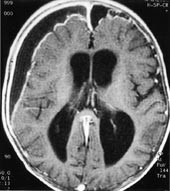

Iskemiske hjerneforandringer avdekkes hos et stort antall pasienter i de høyere aldersgrupper, ofte uten at de relativt iøynefallende MR-funn gir symptomer. Demyelinisering er også ganske lett å fremstille ved en rekke MR-sekvenser, og MR har etter hvert utviklet seg til å bli uunnværlig i diagnostikken av multippel sklerose (15, 16) (fig 5).

Demyelinisering av annen årsak vil også lett kunne demonstreres ved MR , men differensialdiagnostikken mellom sykdommene er ofte vanskelig (16).